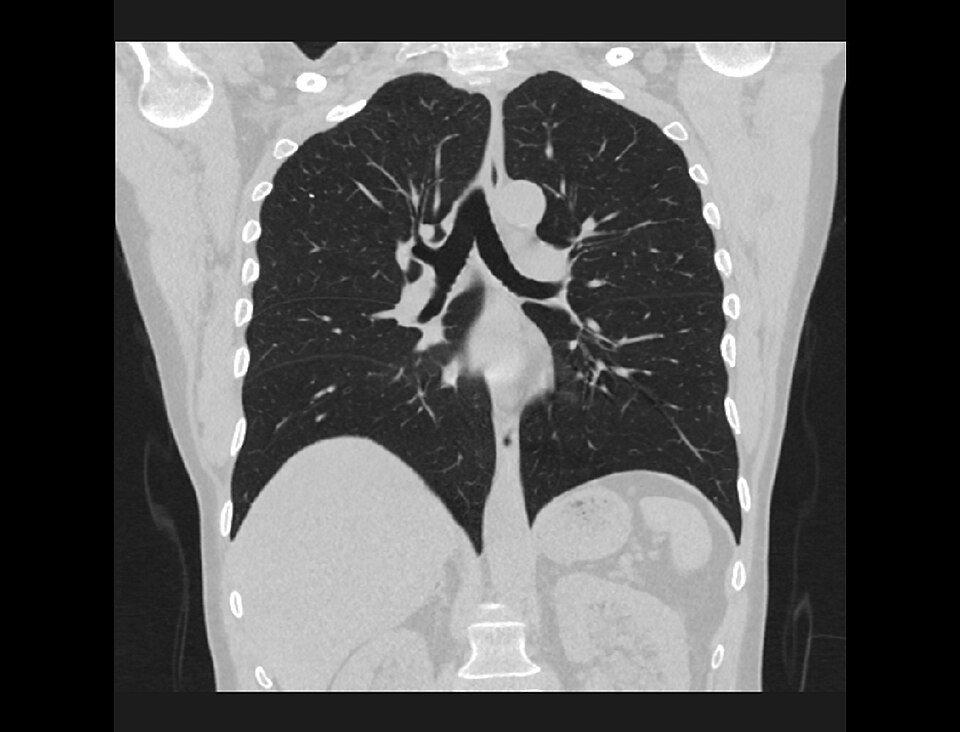

CT Thorax — Coronal Lung Window

Coronal reformatted CT of the chest in lung window showing both lungs, airways, and diaphragm

CT Downloaded 2026-03-15

Ct

Coronal Lung 120 kVp W:1500 L:-600

Wikimedia Commons: COR-2-STND-CHEST-LUNGS.jpg